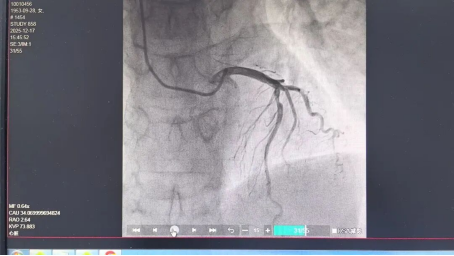

2025年12月17日下午,在该院介入手术室内,由心血管内一科高延主任医疗团队为李阿姨实施了手术。手术经右手桡动脉微创进行,过程顺利。造影图像清晰显示:其心脏的主要供血血管中,前降支近中段存在约70%-75%的中重度狭窄。

然而,血管的狭窄程度并非决定是否需要介入治疗的唯一标准。为了更精确地评估该处狭窄是否真的导致了心肌缺血,团队随即进行了冠状动脉血流储备分数(FFR)测定。结果显示FFR值为0.94,表明在当前状态下,该狭窄并未引起显著的心肌血流灌注不足。